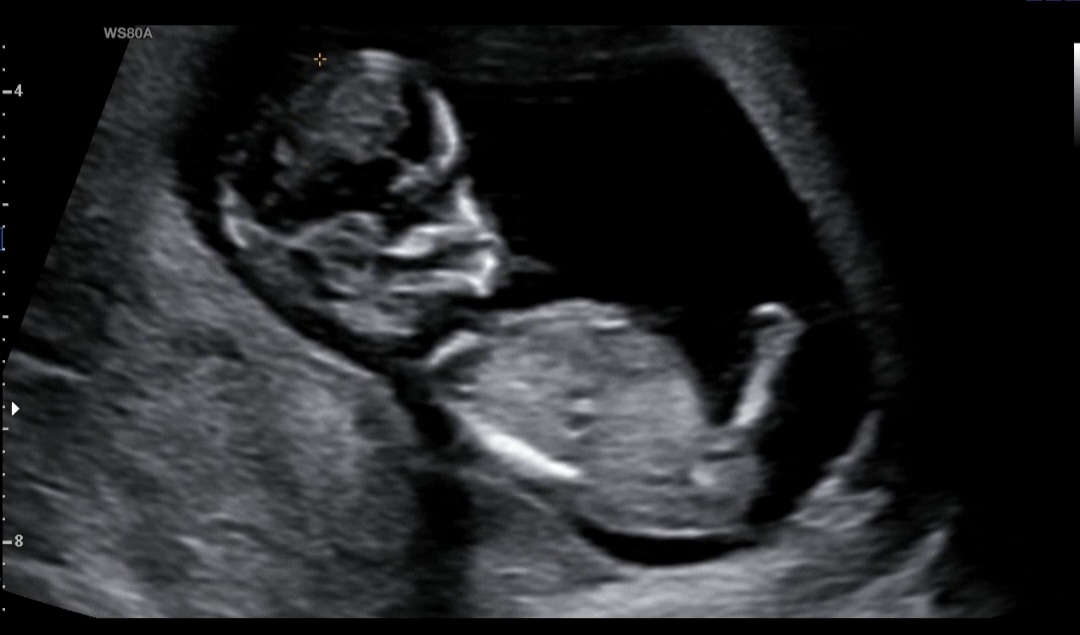

각도법 고수님들 한번봐주셔요😃🫠😉

딸,아들 상관없는데 너무궁금해요 🙊🙊🙊

돌기가 덜 보이기는 것 같긴 해요. 아들 각도 같습니다.